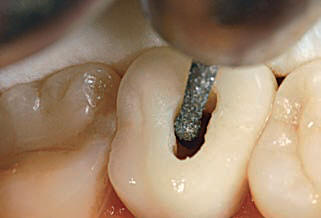

• E: Conformación del acceso a los conductos en el tercio coronal con fresas de Gates Glidden.

El resultado final debe ser una cavidad de acceso que permita a los instrumentos endodóncicos alcanzar los orificios de entrada de los conductos sin interferencia alguna y lo más rectilíneamente posible. Ver imágenes derecha.